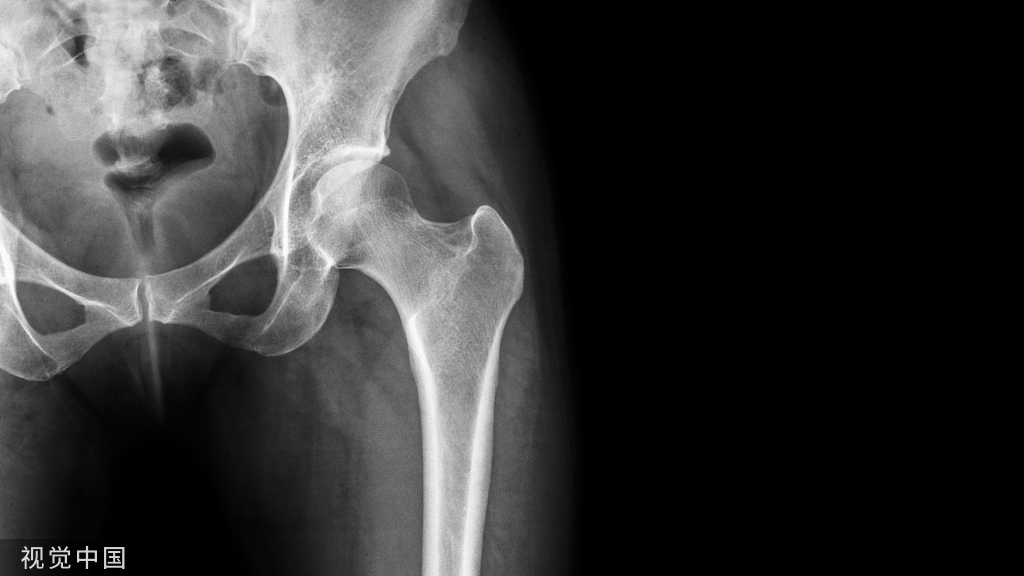

12.大转子滑囊炎

重要肌肉附着点—髂筋膜挛缩—弹响髋

局部疼痛、压痛—活动时加剧—不能侧卧

垂直进针,到达骨面,有积液回抽